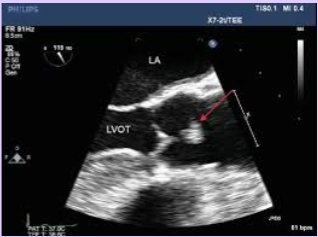

Left atrial appendage thrombus

Caused by stasis of blood within the cavity.

Most common location for atrial thrombus.

Often not seen with TTE; TEE used in patients with CVA.

<p>Caused by stasis of blood within the cavity.</p><p>Most common location for atrial thrombus.</p><p>Often not seen with TTE; TEE used in patients with CVA.</p>